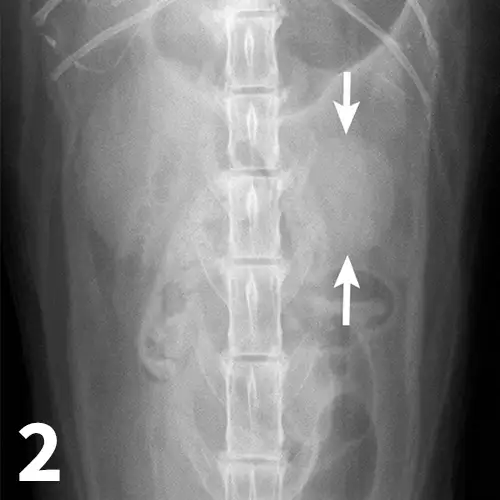

Survey abdominal radiographs (Figures 1 and 2) offer important information on kidney number, size, shape, symmetry, and location, as well as the presence of any mineralized opacities (eg, calcified tissue, nephroliths). The utility of abdominal radiographs is decreased in patients with abdominal fluid or lack of abdominal fat (eg, young or emaciated patients) because of lack of contrast. Excretory urography (IV pyelography), although more invasive, can augment survey radiographs and provide information about renal parenchymal architecture (eg, filling defects associated with cysts or infiltrative disease), the renal pelvis, and ureters as well as a qualitative assessment of global and individual renal excretory function (Figure 3).

Figure 1.

An enlarged left kidney with an irregular shape (arrows) is noted on the VD view of a dog with renal adenocarcinoma. The left kidney measured 4.5 times the length of L2; normal kidney length in the dog is 2.5 to 3.5 times the length of L2.